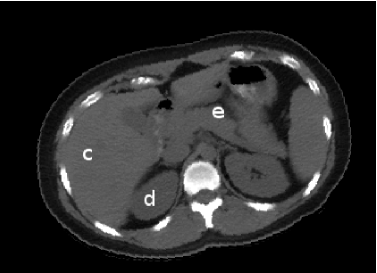

Figure 1 shows annotated landmarks for five different objects (skin, liver, right kidney, left kidney, spleen) in a CT slice of the abdominal region. Note that different number of landmarks are used for different objects considering their size.

Refer to caption

Figure 1. A CT slice of abdominal region with selected objects (skin, liver, spleen, and left and right kidney) is shown on the left. Annotated landmarks for the selected objects are shown on the right.

The b-scale method has been reported to be very useful in image segmentation [2], filtering [16], inhomogeneity correction[17], and image registration [18]. The main idea in b-scale encoding is to determine the size of local structures at every spel under a prespecified scene-dependent region-homogeneity criterion. For example, in Figure 3, the size of the hyperball located at pixel c𝑐c is bigger than that located d𝑑d or e𝑒e, thus the size of the local structure to which pixel c𝑐c belongs is bigger than that to which d𝑑d or e𝑒e belongs. By definition, and also seen from the Figure 3, locally adaptive scale in regions with fine details or in the vicinity of boundaries is small, while it is large in the interior of a large homogeneous object regions.

Refer to caption Refer to caption

Figure 3. (a) A 2D slice from a 3D-CT scene of an abdominal region. Using a suitable region-homogeneity criterion, a local determination is done as to what is the largest disc that can be centered at any point such as c𝑐c within which the intensities are homogeneous. The b-scale at c𝑐c is bigger than that d𝑑d or at e𝑒e. (b) The b-scale scene of the CT abdominal slice in (a).